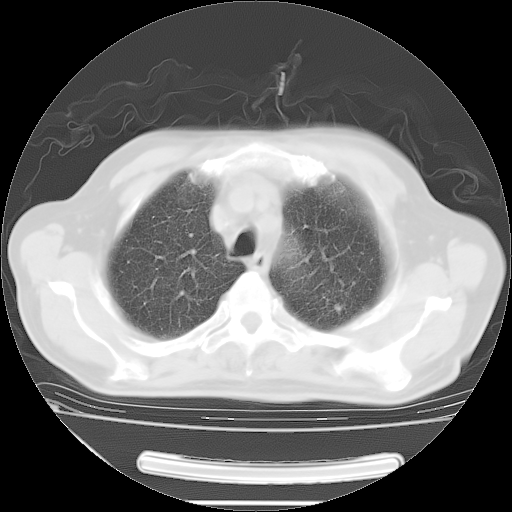

今天复查肺部CT,发现双肺广泛磨玻璃样改变。所以我把3月19日和5月9日相隔50天的肺部CT上传。请大家会诊。

2009年3月19日肺部CT片。

2009年3月19日肺部CT